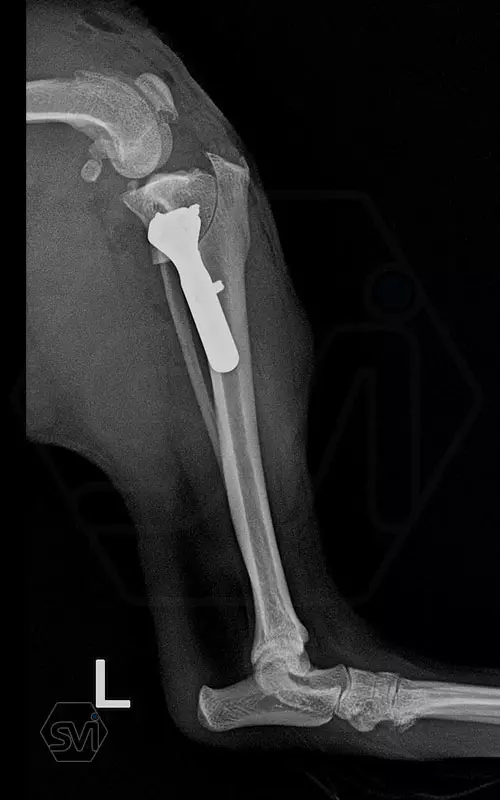

The next step was an osteotomy with a curved saw using an R12 blade and a Smartvet cordless TPLO saw. Since no JIG is used for the operation, the excised bone piece was grasped with a small pointed condylus forceps (small-spitzige) and adjusted to the desired position by the sterile assistant: that an approx. a 2 mm step should be created. This position was fixed with a 1.0 mm K-wire starting from the proximal end of the tuberositas tibiae. The TPLO-M mini plate was used, with a minimal bend, the proximal piece was curved outward for a better fit. The terraced design of the plate was aligned with the 2.2mm step to the bone. Screw insertion order: proximal middle and cranial holes, then distal middle DCP holes (INTRAOP. PICTURE) The three screws were tensioned continuously and alternately, and the temporaly K-wire was removed, thus providing the opportunity for the displacement to be complete and for the osteotomized tibia to assume the position formed by the plate and for compression to develop between bone surfaces. The other screws were then inserted. In our case, the K-wire was no longer returned. (If there is place and way for it, we can put it back a few tenths of a millimeter thicker than the previous one taken out to relieve the crista tibiae. tibiae may break under the load.)

A következő lépés az ívelt fűrésszel való oszteotomia volt, R12 pengét használtunk, és Smartvet akkumlátoros fűrészt. Mivel JIG-et nem használunk a műtéthez, a kivágott csontdarabot kisméretű hegyes condylus-fogóval (kis-spitzige) megragadtuk, és a steril asszisztens a kívánt pozícióba állította: egyrészt a TPA-nak megfelelően elforgatva, majd medialis irányba kiemelve kissé tibia síkjából úgy, hogy egy kb. 2 mm-es lépcső keletkezzen. Ezt a pozíciót egy 1,0 mm -es K szeggel rögzítettük a tuberositas tibiae proximális végétől indítva. A TPLO-M mini lemezt használtuk, egy minimális hajlítással a proximális darabot kifelé görbítettük a jobb illeszkedés végett. A lemez teraszos kialakítását a lépcsőhöz igazítottuk (2,2 mm-es eltolás), és így pozícionáltuk a lemezt. A csavarok behelyezési sorrendje: proximális darab középső és cranialis furat, majd a distalis darab középső DCP furat (INTRAOP. KÉP) A három csavart folyamatosan, felváltva feszítettük, majd a végállapot előtt a pozíciót rögzítő K-szeget a tub. tibiae-ből eltávolítottuk, ezzel biztosítottuk a lehetőségét annak, hogy az eltolás teljes legyen és az oszteotomizált tibia felvegye a lemez által kialakított pozíciót, illetve, hogy kialakuljon a kompresszió csontfelszínek között. A többi csavar behelyezése ezután következett. Esetünkben a K-szeget már nem tettük vissza. (Abban az esetben, ha van hely és mód rá, akkor a kivett előző szegnél néhány tized milliméterrel vastagabbat visszahelyezhetünk a crista tibiae tehermentesítése céljából. Itt ügyelni kell, hogy a szeg soha se menjen a patella egyenes szalagjának tapadási pontja alá, mert a tub. tibiae letörhet a terhelés hatására.)